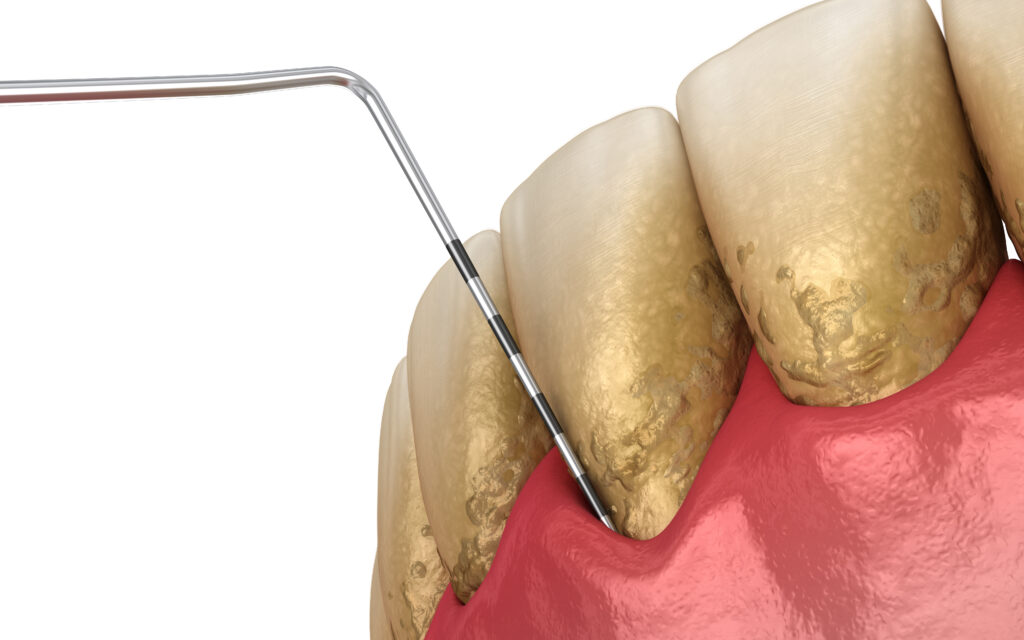

③ポケット検査

専用の器具を使い、歯ぐきの溝(歯周ポケット)の深さを測ります。 歯周ポケットの深さや、検査時の出血の有無で歯周病の進行度や炎症の有無を知ることができます。 一般的に、健康だとされるポケットの深さは3mm以下とされており、4mm以上になると歯周病だと判断します。 歯周ポケットの深さは深ければ深いほど、歯周病が進行しているということになります。 歯周病のなかにも、軽度のものから重度のものまでさまざまあり、かなり進行してしまうと歯を残すことが難しくなる場合もあるので注意が必要です。

歯と歯ぐきの境目に付着している、歯石や歯周病の原因となるバイオフィルムという汚れを取り除きます。 歯石やバイオフィルムは一度付着してしまうと、ブラッシングではなかなか除去することができません。歯科医院で専用の器具を使って除去する必要があります。

歯石を除去するときには、「手用スケーラー」と「超音波スケーラー」という器具を、必要に応じて使い分けていきます。